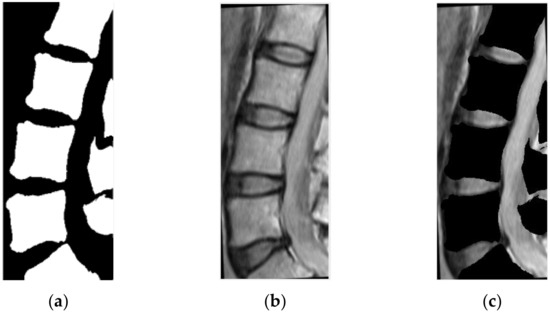

2.2. CT Segmentation for Vertebral Boundary Extraction

3.2. Results and Discussion